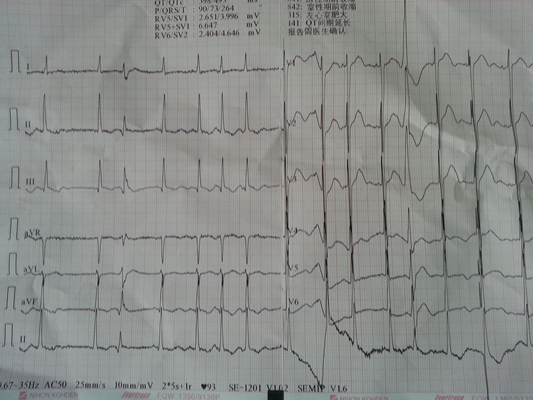

預激綜合症圖片

預激綜合徵心電圖 (9)

預激綜合徵心電圖 (90)

預激綜合徵心電圖 (91)

預激綜合徵心電圖 (92)

預激綜合徵心電圖 (93)

預激綜合徵心電圖 (94)

預激綜合徵心電圖 (95)

預激綜合徵心電圖 (96)

A:預激綜合徵典型的心電圖表現是竇性心搏的PR間期縮短,短於0.12s,而且導聯的QRS波群時間超過0.12s。QRS波群起始部分會有粗鈍,終末部分正常,甚至會導致ST-T波型呈現繼發性的改變,甚至於QRS波群主波方向相反。預激綜合徵是指心房……

A:預激綜合徵是很少見的心律失常,是房室傳導異常的一種類型,提早興奮心室的一部分或全部,引起心室肌提前激動,常合併室上性心動過速。心電圖可見PR間期縮短小於0.12秒;QRS時限延長0.11秒以上;QRS波群起始部粗鈍,繼發性ST-T改變。沒有……

A:預激綜合徵合併房速的時候,心電圖可以出現快速而且寬大畸形的QRS波群,有點類似於室性心動過速,典型的預激波有可能會被覆蓋。合併房速的時候會有極快速的心室率、QRS波群會寬大畸形,也有可能比較易變和複雜。患有預激綜合症合併房速,如果有明顯的心……